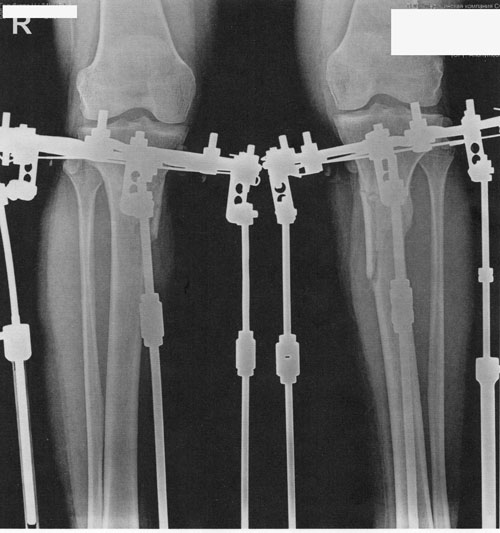

ножки в аппаратах, в день снятия.